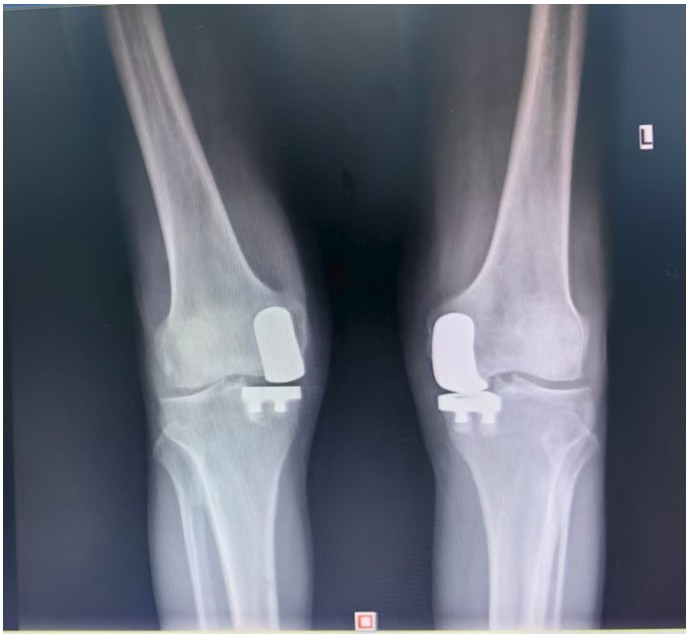

據(jù)了解,患者1年前無明顯誘因出現(xiàn)雙膝關(guān)節(jié)疼痛,以右側(cè)膝關(guān)節(jié)為主,近5個月來雙膝關(guān)節(jié)疼痛明顯加重,不但日常行走困難,生活質(zhì)量更是受到極大影響。經(jīng)多家醫(yī)院治療效果均不理想,了解到衡陽市中心醫(yī)院關(guān)節(jié)外科在關(guān)節(jié)置換領(lǐng)域擁有豐富的臨床經(jīng)驗和良好的患者口碑,毅然決定赴衡求醫(yī)。醫(yī)生發(fā)現(xiàn)患者雙膝關(guān)節(jié)已有內(nèi)翻畸形,關(guān)節(jié)內(nèi)側(cè)骨性膨大,X線提示雙膝退行性病變,雙膝內(nèi)側(cè)間隙明顯狹窄,手術(shù)為最佳治療方式。為了達(dá)到根治目的,羅湘平主任醫(yī)師、彭健副主任醫(yī)師為患者進(jìn)行了詳細(xì)查體及綜合評估,術(shù)前組織開展多學(xué)科討論(MDT)。考慮到易叔叔的膝關(guān)節(jié)骨關(guān)節(jié)炎僅局限于內(nèi)側(cè),外側(cè)間室軟骨良好,若采用全膝關(guān)節(jié)置換術(shù)會將失去正常關(guān)節(jié)間室的軟骨與韌帶,創(chuàng)傷較大,便為其制定了右膝關(guān)節(jié)單髁置換手術(shù)治療方案。在充分完善術(shù)前準(zhǔn)備后,羅湘平主任、彭健副主任醫(yī)師團(tuán)隊為患者實施了右側(cè)膝關(guān)節(jié)單髁置換術(shù)。手術(shù)過程順利,團(tuán)隊?wèi)?yīng)用微創(chuàng)術(shù)式(MIS)及“精準(zhǔn)間隙平衡技術(shù)”,最大程度減少了手術(shù)創(chuàng)傷,為術(shù)后快速康復(fù)奠定了堅實基礎(chǔ),術(shù)后第二天即可借助助行器下地活動。6天后團(tuán)隊順利為患者實施了左側(cè)膝關(guān)節(jié)單髁置換手術(shù)。目前,易叔叔在關(guān)節(jié)外科醫(yī)護(hù)團(tuán)隊的精心指導(dǎo)和康復(fù)治療下,恢復(fù)情況良好,雙側(cè)膝關(guān)節(jié)活動度輕松達(dá)到90°,膝關(guān)節(jié)功能顯著改善,能夠獨立下地行走,對手術(shù)效果非常滿意,已于9月10日順利出院。

羅湘平主任介紹,膝單髁置換術(shù)是針對膝關(guān)節(jié)單側(cè)間室病變的微創(chuàng)手術(shù),該術(shù)式通過置換單側(cè)股骨或脛骨受損軟骨表面,保留交叉韌帶及正常骨質(zhì)結(jié)構(gòu),因創(chuàng)傷小、恢復(fù)快被稱為膝關(guān)節(jié)置換中的“補(bǔ)牙”技術(shù),適用于單間室骨關(guān)節(jié)炎且韌帶功能完整的患者。膝關(guān)節(jié)單髁置換為特定的膝關(guān)節(jié)疾病患者提供了一種較為理想的治療選擇,它以較小的手術(shù)創(chuàng)傷、良好的術(shù)后功能恢復(fù)效果,幫助患者緩解疼痛,恢復(fù)正常的生活和活動能力。